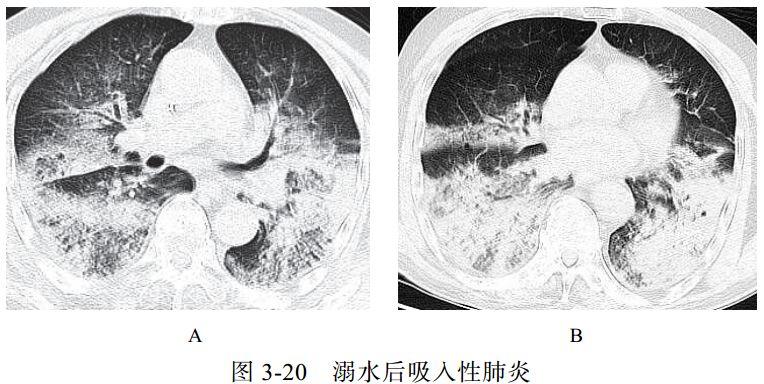

(六)吸入性肺炎

吸入性肺炎常见于慢性衰弱性疾病、咽和食管结构异常、全身麻醉等患者。吸入性肺炎可导致肺损伤或肺部炎症性疾病,如肺内节段性肺炎、支气管肺炎、肺脓肿和脓胸等。老年人存在隐性误吸。

影像学表现:无明显特异性特征,需结合病史与临床表现来做出诊断(图 3-20)。

图片